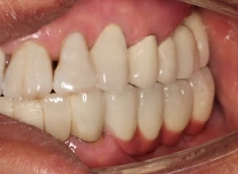

• Tình trạng răng trước đây:Mất nhiều răng ở cả 2 hàm, bị viêm nha chu nhiễm trùng

Từng là người rất chủ quan về vấn đề vệ sinh răng miệng cộng thêm việc ăn uống nóng lạnh quá nhiều khiến cho chú Đình Hảo hư hỏng và mất nhiều răng. Dẫn tới sức khỏe và tâm lý của chú cũng bị ảnh hưởng.

Chú Hảo là người rất quan trọng những bữa cơm cùng gia đình, nhưng từ ngày mất răng chú hầu như không còn cảm giác ăn uống ngon miệng nữa. Thay vào đó là sự đau nhức, khó chịu, thỉnh thoảng còn sưng viêm làm chú thêm mệt mỏi.